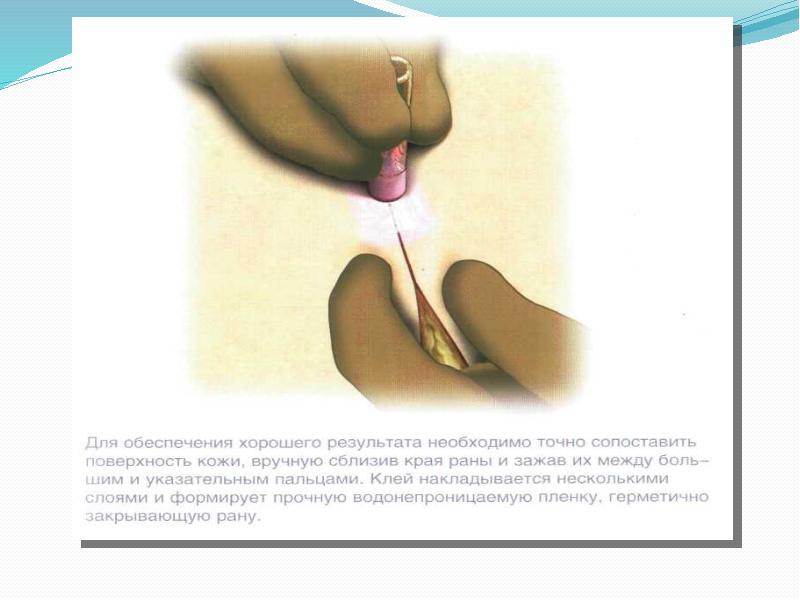

- 67. Неинвазивные методы закрытия ран Сведение краев раны может быть достигнуто лейкопластырем

- 69. Для сведения краев раны в последние годы пользуются атразипом — атравматическим